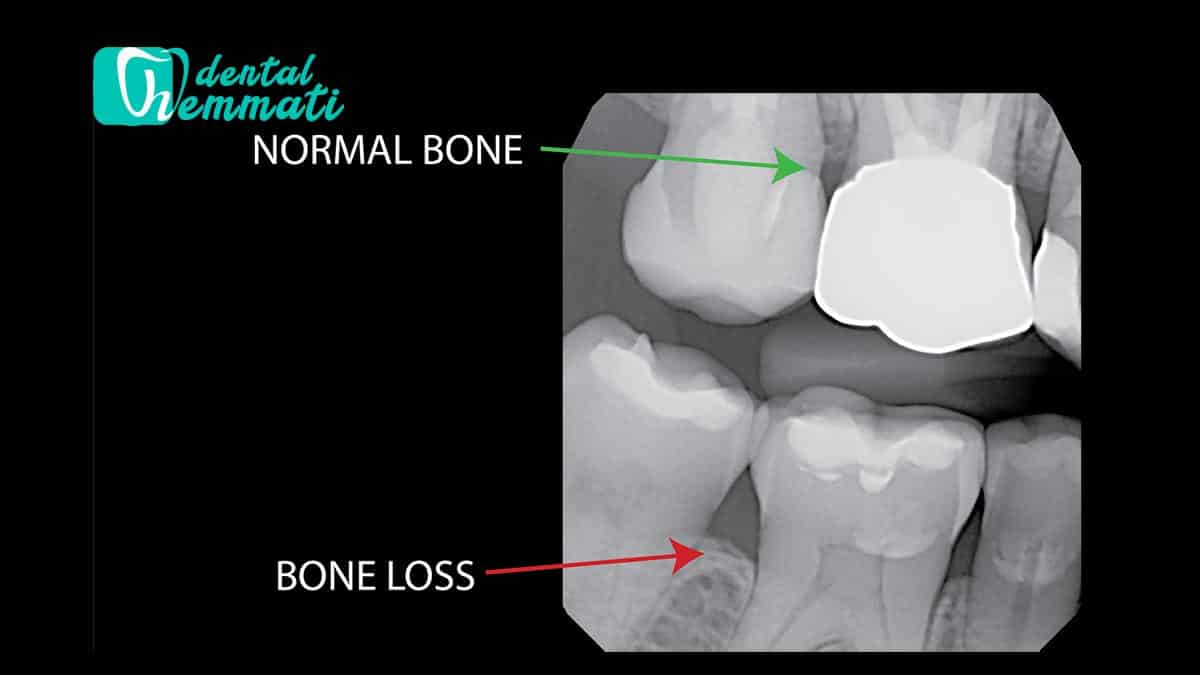

عفونتهای پیشرفته لثه (پریودنتیت): که موجب تخریب استخوان اطراف دندان میشود.

استخوان فک ضعیف